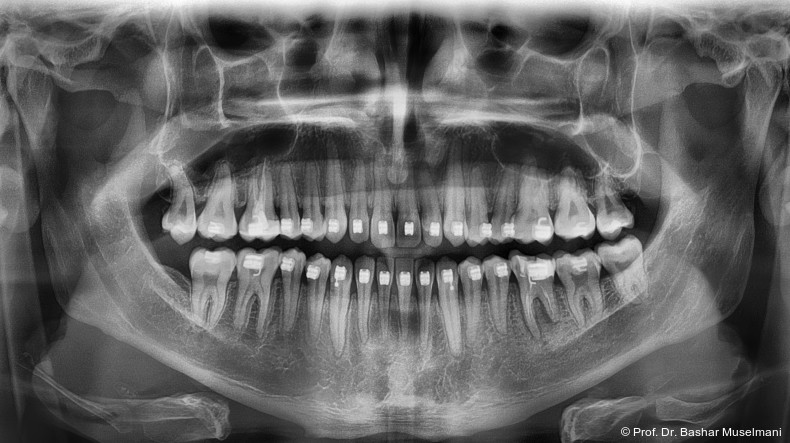

Der Patient (28 Jahre 8 Monate) stellte sich mit einer skelettalen Klasse III sowie einer Mittellinienabweichung nach links vor.

Fernröntgenologische Befunde (Behandlungsbeginn)

• SNA: 81,5°

• SNB: 84,3°

• ANB: −4,9°

• Wits-Wert: −8,4 mm

Klinische Befunde

• leicht konkaves Gesichts- und Mundprofil

• posterior positionierter Unterkiefer (VW)

• retroinkliniert stehende Unterkieferfront

Die Abbildungen 1 bis 3 zeigen die initiale klinische und radiologische Ausgangssituation.